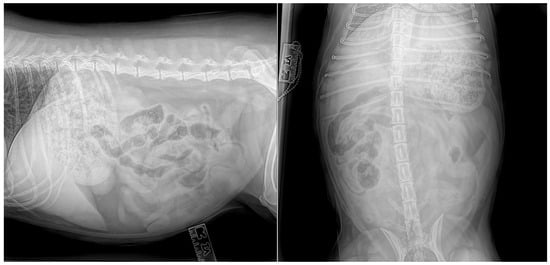

On presentation, the dog was mildly depressed, weighed 20.3 kg, and had a body condition of 6/9. Her rectal temperature was 37.7 degrees, her heart rate was 100 beats per minute, and her respiratory rate was 32 breaths per minute. Her mucous membranes were pink, mildly injected, and moist with normal capillary refill (<1 s). The abdomen was tense, and there was marked pain and vocalisation with mid-abdominal palpation. Packed cell volume and total solids were within normal limits at 43% (37–55%) and 75 g/L (reference range, 55–75 g/L), respectively. A complete blood count (IDEXX ProCyte Dx, Westbrook, ME, USA) and biochemistry (IDEXX Catalyst One, Westbrook, ME, USA) were within normal limits. Venous blood gas analysis (Radiometer, Copenhagen, Denmark) revealed mild hypercapnia (pCO2 44.7, range 34.0–39.0), mild hypokalaemia (3.3, range 3.4–5.3), and mild hyperglycaemia (6.7, range 3.6–6.2). Lactate was within normal limits. Ultrasound-guided abdominocentesis was performed, and the abdominal fluid collected was an acellular high-protein transudate with a total protein of 43 g/L (refractometer). The dog was hospitalised for initial supportive care. An intravenous (IV) catheter was placed, and a lactated ringer solution supplemented with 10 mmol potassium chloride was administered at a rate of 100 mL/h. A fentanyl constant rate infusion was started at 3 ug/kg/h, and maropitant 1 mg/kg was administered IV. Three-view abdominal radiographs were performed to identify a moderate amount of gas and fluid within the stomach and intestines with mild dilation of both organs (Figure 1). No foreign body was identified, and faeces were present within the colon. There were good serosal details, and the findings were not conclusive of an obstructive pattern. Differential diagnoses included radiolucent gastric or intestinal foreign bodies, gastroenteritis, acute pancreatitis, or peritonitis.

Figure 1. Abdominal radiographs revealed dilated intestines and mixed heterogeneous gas and soft tissue attenuating material within the stomach without evidence of a foreign body or obstructive pattern.